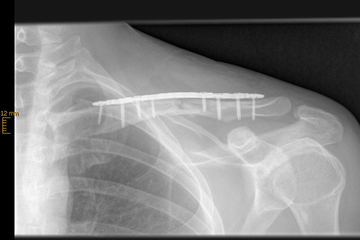

Klavikulafraktur (Schlüsselbeinbruch)

Die Klavikulafraktur ist eine typische Fraktur des jungen Patienten. Rad- und Motorradfahrer, Wintersportler und Kontaktsportler sind die typischen betroffenen Patienten.

Viele Schlüsselbeinbrüche können ohne Operation behandelt werden, wenn die Frakturstücken keine wesentliche Verschiebung (Dislokation) aufweisen. Der betroffene Arm wird in einer Armschlinge für ca. 3-4 Wochen ruhiggestellt, parallel wird mit physiotherapeutischen Behandlungen begonnen. Die Behandlungsdauer beträgt ca. 8 Wochen. Kommt es jedoch zu einer deutlichen Verschiebung der Frakturenden (um mehr als die Breite des Schlüsselbeins) und tritt dadurch eine Verkürzung oder ein Abknicken des Schlüsselbeins auf, besteht die Indikation zur Operation. Gleiches gilt auch für eine Fraktur des Schlüsselbeins mit vielen Bruchstücken (Fragmenten).